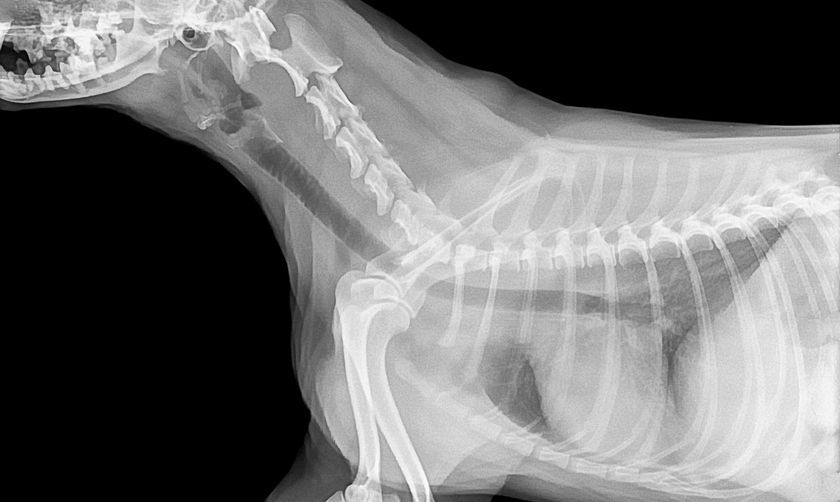

Une radiographie pulmonaire permet de détecter une inflammation des voies respiratoires et des structures adjacentes et de rechercher des maladies des voies respiratoires supérieures telles que la bronchite ou la pneumonie.